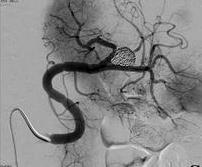

脾动脉瘤的血管内治疗

脾动脉瘤的血管内治疗技术

脾动脉主干动脉瘤

脾门动脉瘤栓塞

近端脾动脉瘤栓塞